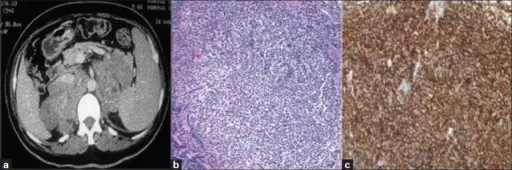

Pheochromocytoma

A particular kind of neuroendocrine tumor (NET) known as a pheochromocytoma develops from chromaffin cells.

Chromaffin cells are located in the adrenal glands and create hormones that the body requires.

Clinical features of pheochromocytoma results from elevated serum catecholamine levels.

Increased 24-hour urine production and serum metanephrine levels are used to diagnose the disease.

Medical excision is used as a treatment of choice.

Pheochromocytoma is associated with other medical conditions such as:

- Von Hippel-Lindau disease

- Neurofibromatosis type 1 (NF1)

- Multiple endocrine neoplasia (MEN) types 2A and 2B (MEN 2A and MEN 2B)